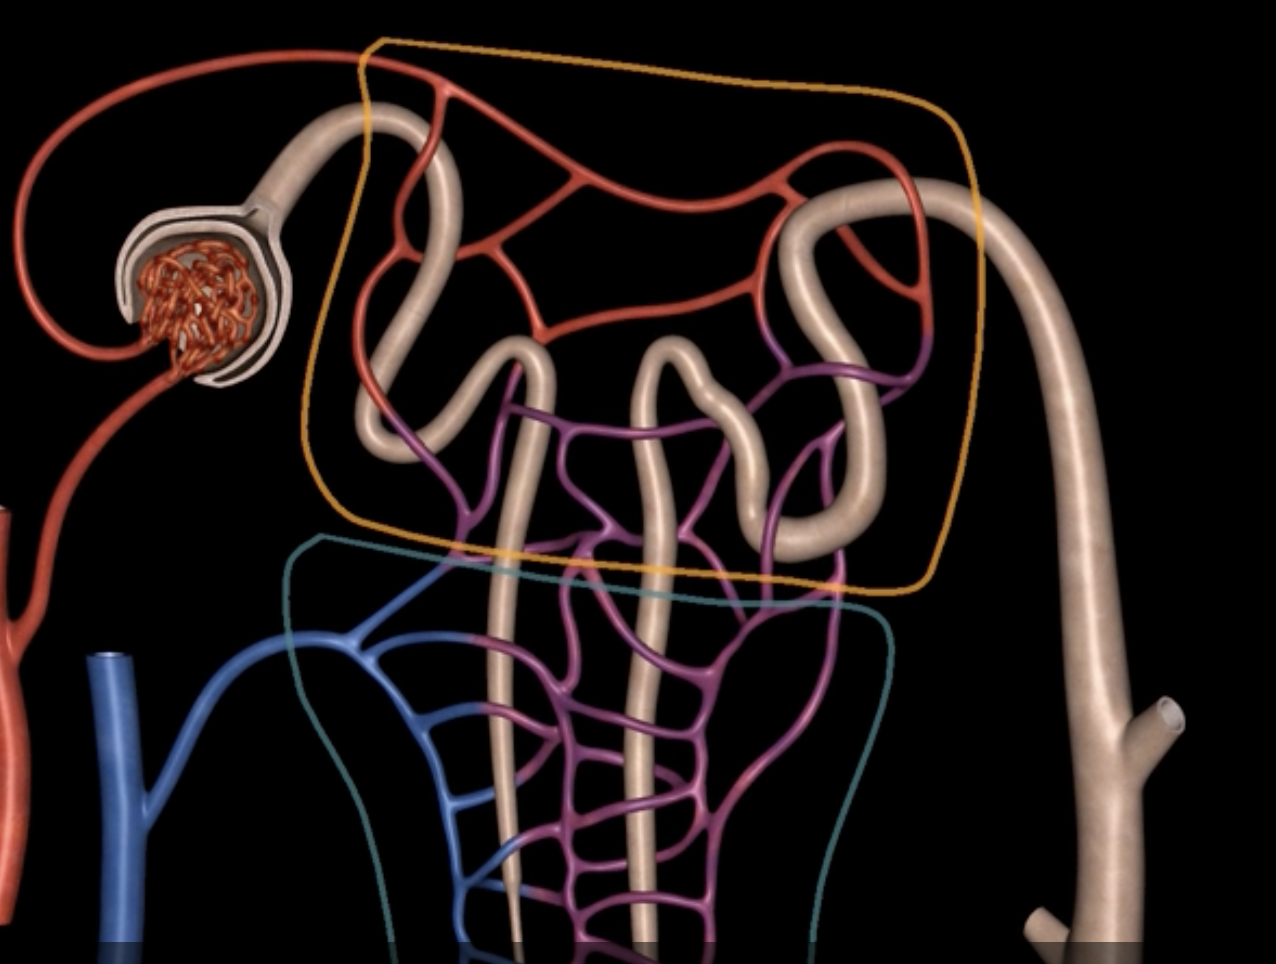

name: proximal convoluted tubule

function: tubular reabsorption

lining: simple cuboidal epithelium w/ microvilli for increased surface area

loop of Henle

red: descending limb

blue: ascending limb

red:

blue:

reabsorb ions

blue’s function

reabsorb water

red’s function

green: thick segment lined with simple cuboidal

purple: thin segment lined with simple squamous

green:

purple:

name: distal convoluted tubule

function: secretion of H+ and K+ ions

lining: simple cuboidal, sparse microvilli

name: collecting duct

function: last structure to modify fluid, but only under the influence of only ADH and aldosterone

lining: simple cuboidal epithelium